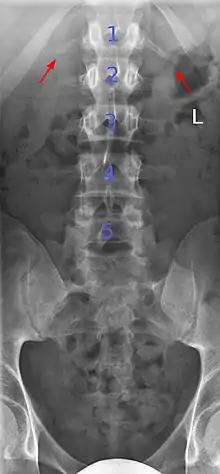

Lumbarization of sacral vertebra 1, seen as 6 vertebrae that do not connect to ribs.

Lumbarization is an anomaly in the spine. It is defined by the nonfusion of the first and second segments of the sacrum. The lumbar spine subsequently appears to have six vertebrae or segments, not five. This sixth lumbar vertebra is known as a transitional vertebra. Conversely the sacrum appears to have only four segments instead of its designated five segments. Lumbosacral transitional vertebrae consist of the process of the last lumbar vertebra fusing with the first sacral segment. [1] While only around 10 percent of adults have a spinal abnormality due to genetics, a sixth lumbar vertebra is one of the more common abnormalities. [2]

Sacralization of the L5 vertebra is seen at the lower right of the image.

Sacralization of the fifth lumbar vertebra (or sacralization) is a congenital anomaly, in which the transverse process of the last lumbar vertebra (L5) fuses to the sacrum on one side or both, or to ilium, or both. These anomalies are observed at about 3.5 percent of people, and it is usually bilateral but can be unilateral or incomplete (ipsilateral or contralateral rudimentary facets) as well. Although sacralization may be a cause of low back pain, it is asymptomatic in many cases (especially bilateral type). Low back pain in these cases most likely occurs due to biomechanics. In sacralization, the L5-S1 intervertebral disc may be thin and narrow. This abnormality is found by X-ray.